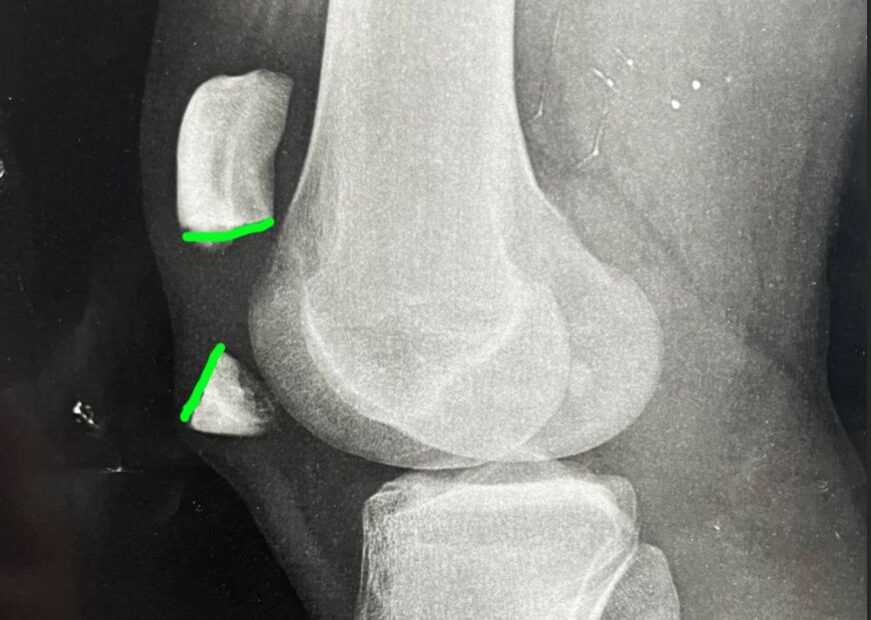

Um excelente e moderno recurso é o laser para joelho, existem diversos tratamentos, entre eles a osteoartrite. Novas tecnologias são sempre muito bem vindas. Nesse… Continue a ler »Laser para joelho – Tratamento da Osteoartrite